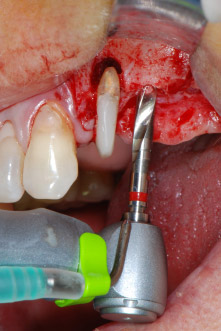

Implantatmotor

Abb. 8: Der nächste Schritt ist die rotierende Präparation des Implantatbetts bis kurz unterhalb des Sinusbodens an Position 25, die mit einem weiterentwickelten Implantatmotor erfolgte.

Im folgenden Schritt wurde das jeweilige Implantatbett an den Positionen 25 und 26 mit rotierenden Instrumenten in einem Winkelstück mit einem Übersetzungsverhältnis von 20:1 (WS-75 L G, W&H) und einem vor Kurzem aktualisierten leistungsstarken Implantatmotor präpariert (Implantmed, W&H) (Abb. 8 und 19).